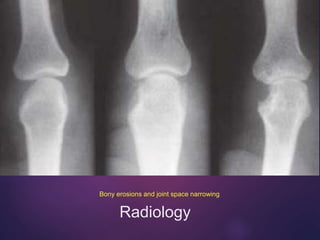

Radiology

Bony erosions and joint space narrowing

• Marginal erosions and joint space narrowing on x-ray